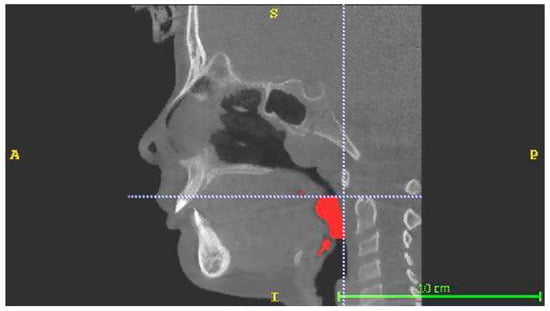

The CBCTs were used to perform digitized volumetric analysis using ITK-SNAP 3D segmentation software (Version 3.6.0, © 1998–2007, Paul A. Yushkevich, Guido Gerig). This software allows the user to select the space of the airways based on air radiological intensity values and then to delimit these spaces according to the anatomical landmarks considered, obtaining clear and precise limits. In this study, two volumes, delimited by a plane parallel to the Frankfurt plane, were defined and quantified:

Retroglossal volume (RGV), limited superiorly by a plane passing through the most postero-inferior point of the soft palate and inferiorly by a plane passing through the most postero-superior point of the epiglottis. This volume also included the volumetric portions facing the oral cavity between the soft palate and the lingual root and between the epiglottis and the lingual root (Figure 2).

Figure 2. Retroglossal Volume (RGV).